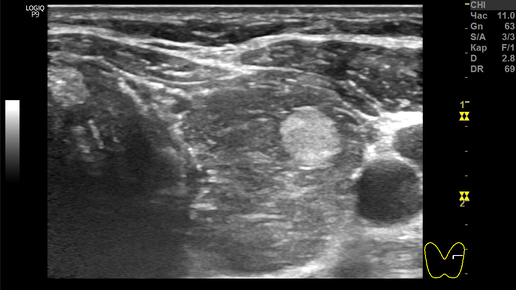

Узлы Щитовидной железы, при которых пункционная биопсия не нужна!

Если раньше рекомендовали пункцию любого узла, размеры которого были бюольше 10 мм, то сейчас многое изменилось. К выбору показания для пункции стали подходить на основании достоверных признаков рака или доброкачественности. Эти признаки выявляют при УЗИ щитовидной железы. Существуют три варианта узлов, при которых пункция не показана! К сожалению, о них не всегда знают специалисты УЗИ. В результате, пациенты при абсолютно доброкачественных узлах выполняют несколько раз повторные УЗИ и пункционную биопсию, подвергаются психической травме от переживаний...